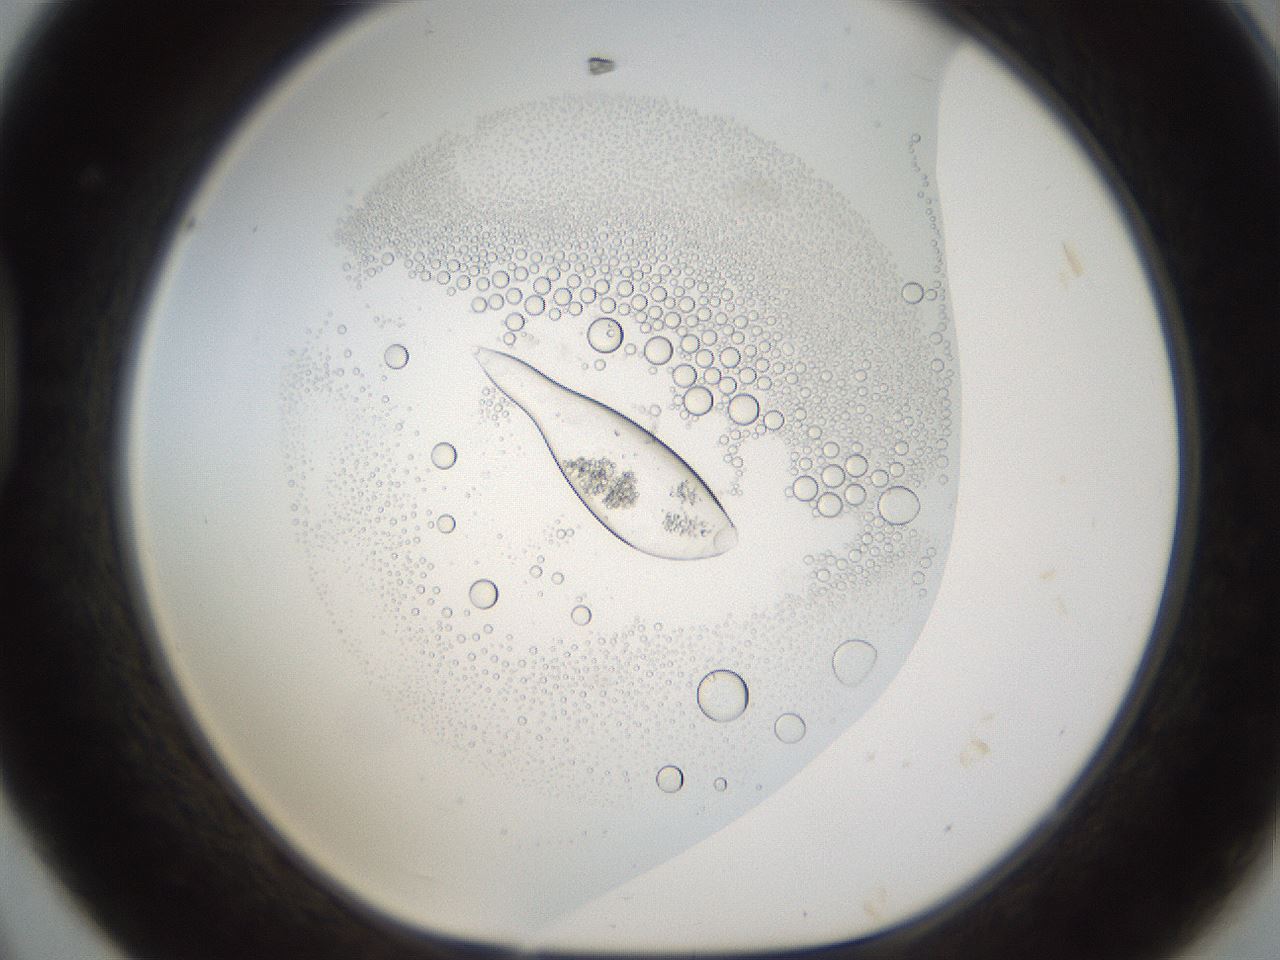

folderID214_plateID1214_batchID3712_wellNum44_profileID1_d1_r69622_ef.jpg